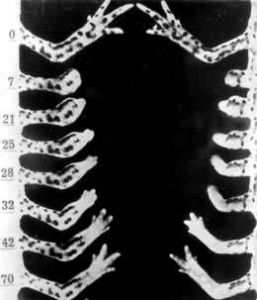

以廢舊金屬製品和工業生產過程中的金屬廢料為原料煉製而成的有色金屬及其合金。又稱二次有色金屬。早在銅器時代就使用再生有色金屬,即將廢舊金屬器物回爐重熔。到20世紀,出現了專業化的再生金屬工業,並得到蓬勃發展。金屬,特別是有色金屬的廢料回收,有利於環境保護和資源的利用,具有投資省、能耗少、經濟效益顯著的特點。因而,再生有色金屬產量在各國總產量中的比重逐年上升(見表和圖1)。中國也興建了再生有色金屬工廠。

再生有色金屬配圖